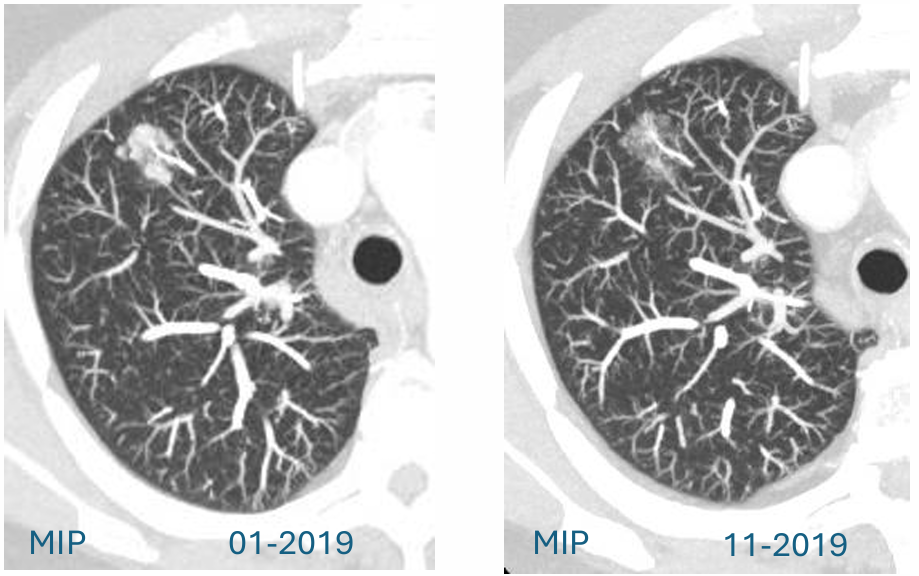

中期随访:误导性的病灶缩小

2019年11月,CT随访:距离初次发现约10个月后,CT复查显示令人意外的结果:结节明显缩小。影像表现:原有的亚实性(磨玻璃)成分变得“几乎难以辨认”。更重要的是,原先大于8mm的实性成分已缩小至仅3mm。这种显著的消退强烈指向炎性或感染性病变,在临床实践中,这通常被视为良性过程的有力证据,大多数情况下可能导致停止进一步的肿瘤相关随访。

f41356ff-d4f5-4bfc-adf2-2ea7abd96013.png